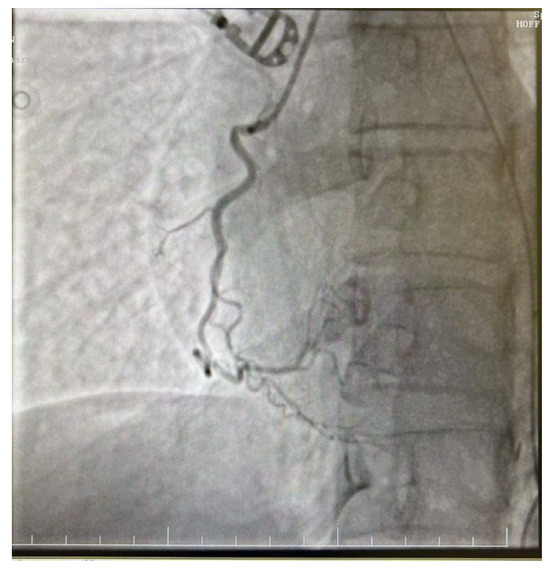

The decision was made to perform a coronarography, which showed no signs of acute or chronic coronary obstruction (Figure 5 and Figure 6). The patient was put on a continuous infusion of 0.01 micrograms/kg/min of noradrenaline and 1.8 mcg/kg/min of dobutamine with 40 mg of enoxaparin given the next day. She remained intubated for 48 h and the improvement of her hemodynamic status allowed the discontinuation of the inotropic medication the following day. After the steady improvement of the respiratory and cardiac functions, the patient’s clinical status allowed extubation with spontaneous breathing. The patient was started on the standard therapy for cardiac insufficiency, consisting of beta blockers, antiarrhythmic therapy, Angiotensin-converting enzyme (ACE) inhibitors and levosimendan. The following echocardiogram showed slow but steady improvement in the cardiac function. She was discharged from intensive care on day 6 and from the hospital on day 10. The echocardiogram conducted on the day she was discharged from the ICU revealed an EF of 25%, with akinesia of the ventricular apex and medio/apical segments, with no right ventricular dilatation and mild mitral regurgitation. On day 9 after HIPEC, the echocardiogram revealed an EF of 30–35% with hypokinesis of the apex and middle-to-apical segments of the heart. The patient did not complain of angina or dyspnea and tolerated lying in the supine position. She was discharged from the hospital on a combination of beta blockers, antiarrhythmic medication and ACE inhibitors, with a follow-up echocardiogram after one month.

Figure 6.

Right dominant coronary system without significant angiographic lesions.